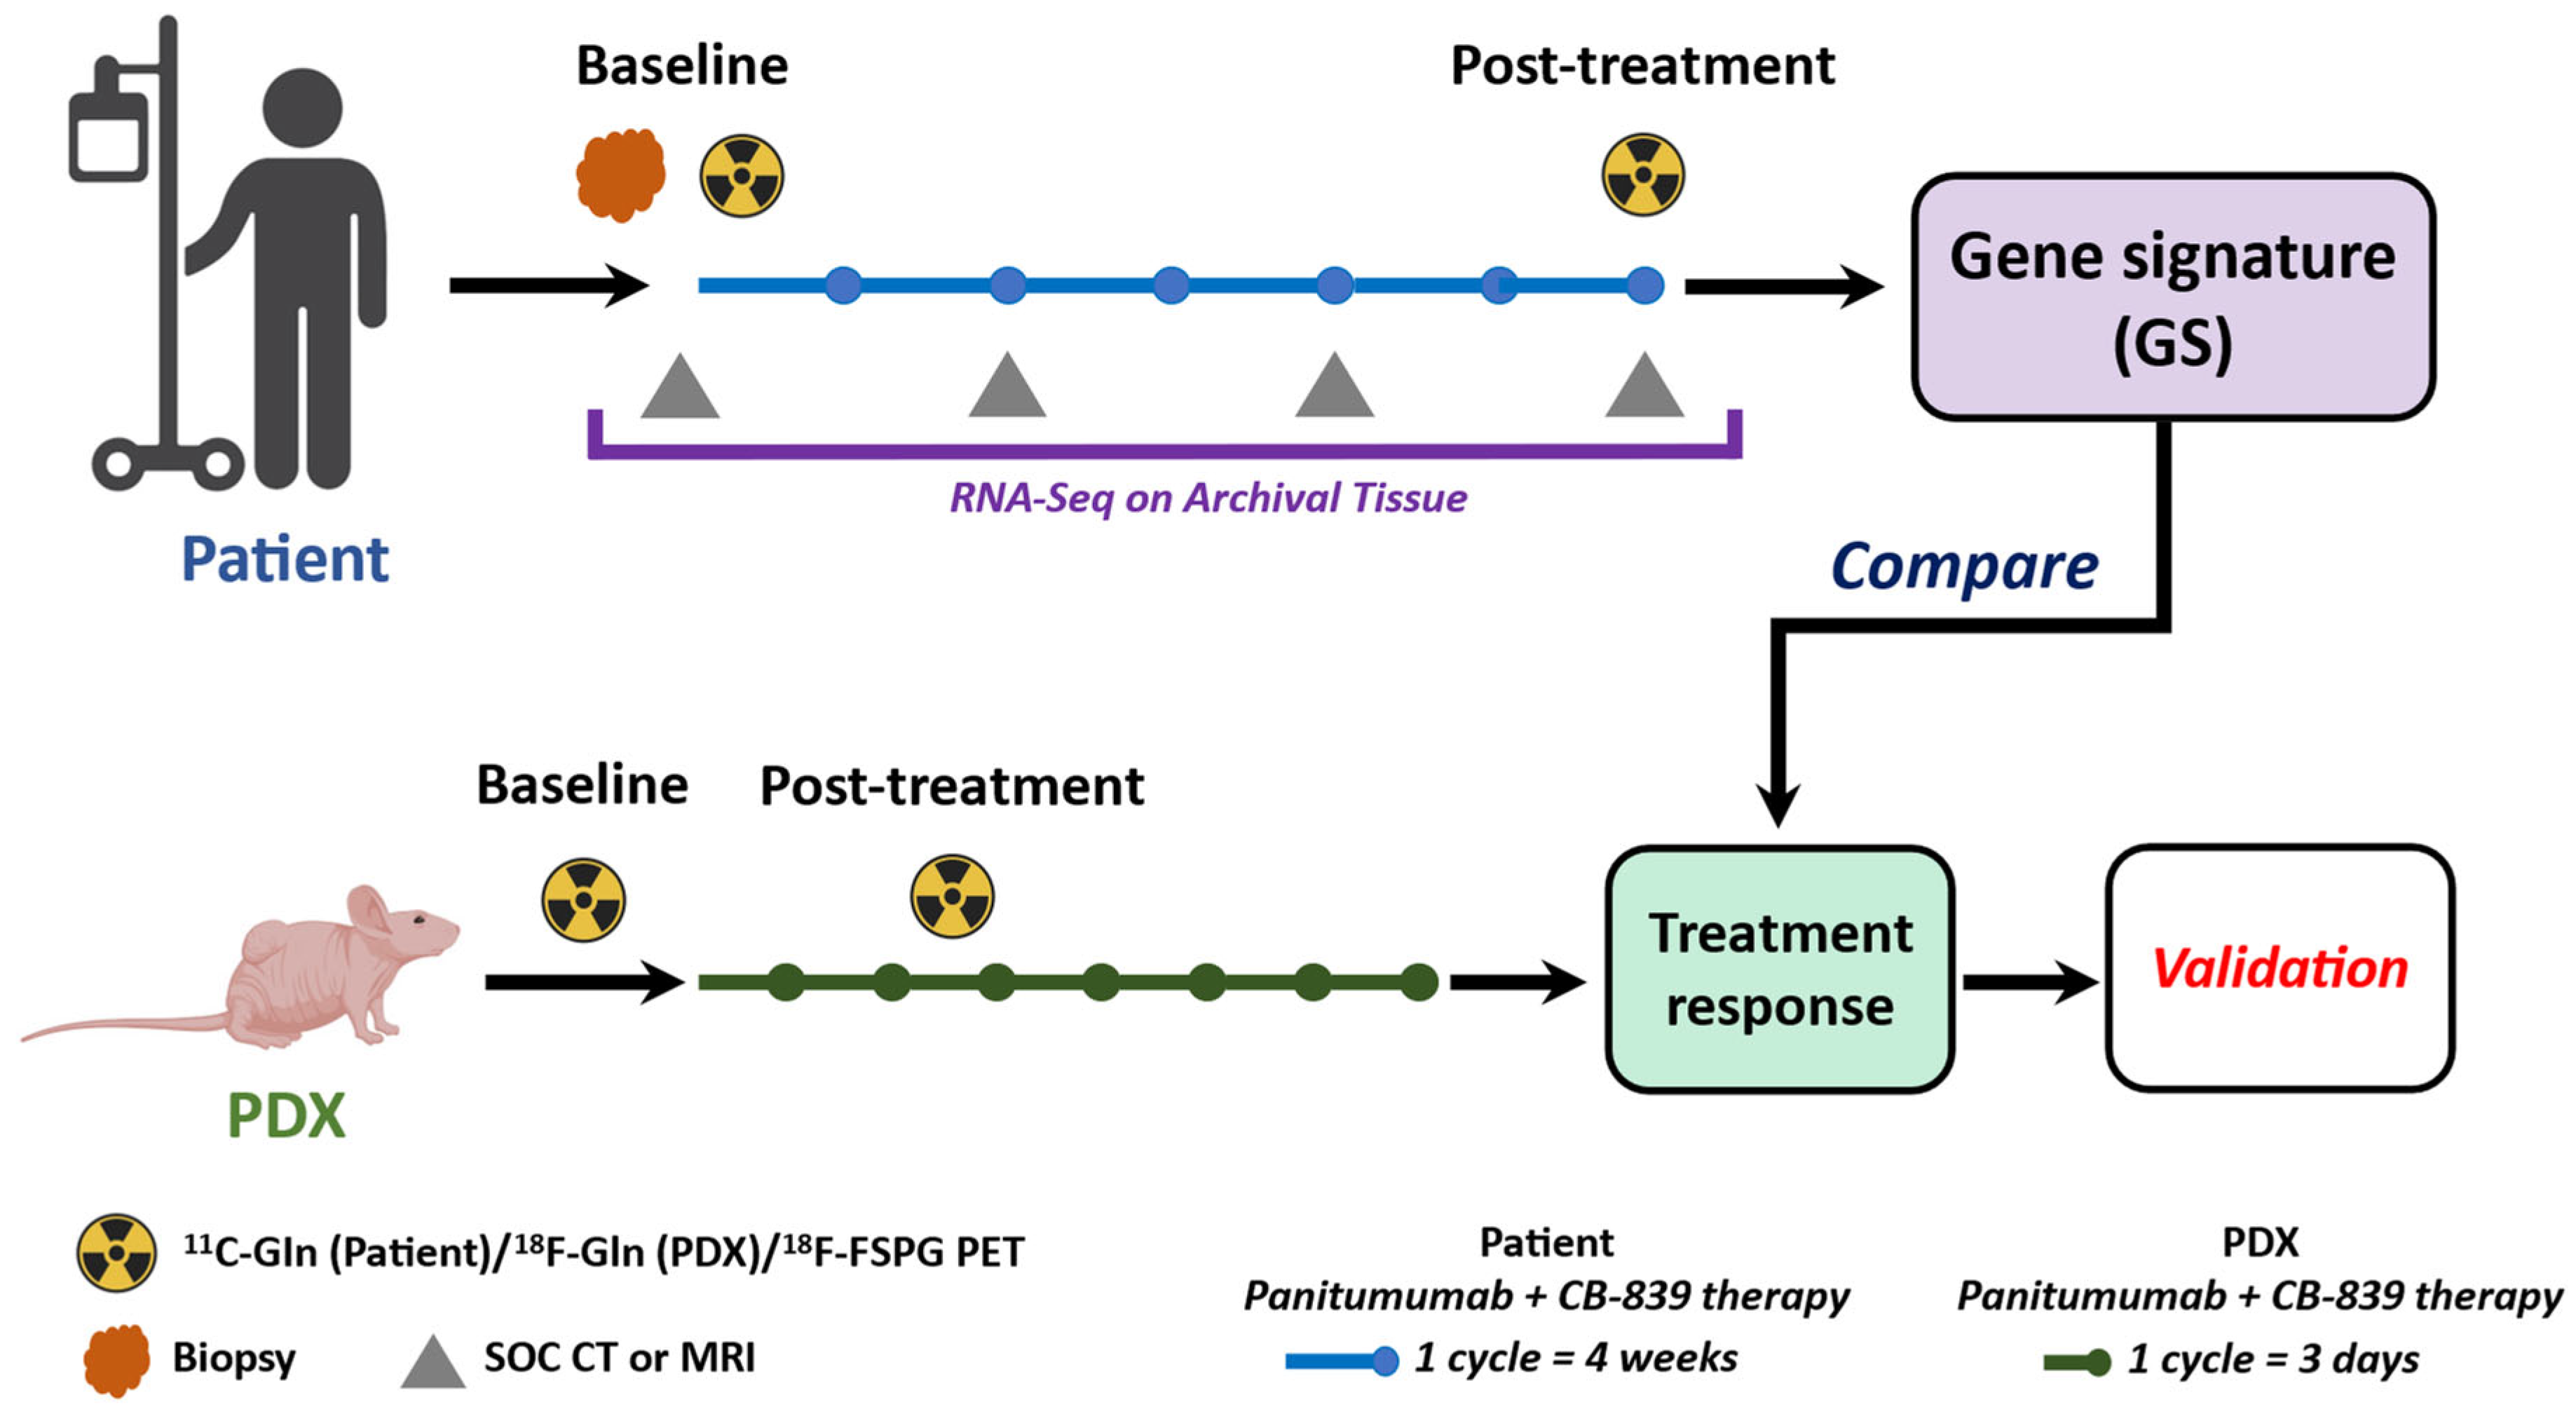

2.3. The MDACC PET Imaging Resource to Enhance Delivery of Individualized Cancer Therapeutics (PREDICT) for Wild-Type KRAS Colorectal Cancer